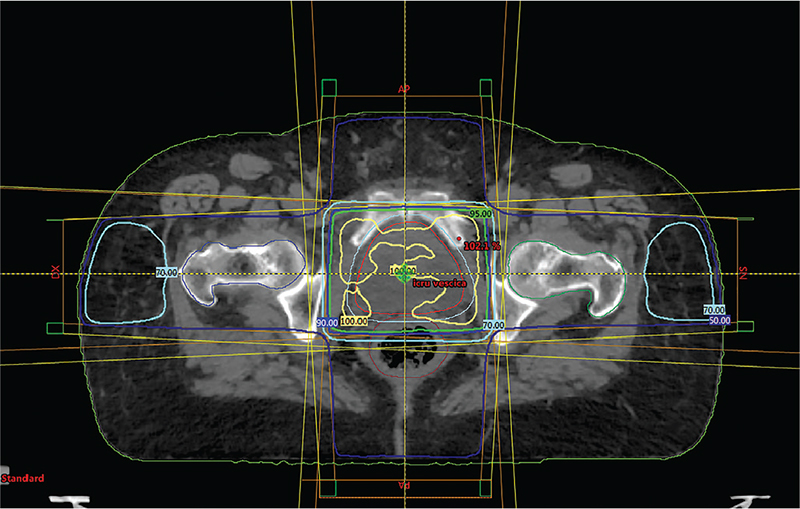

Dalle immagini sottostanti si evince come con la tecnica box, utilizzando cioè quattro fasci di fotoni con angoli di entrata ortogonali tra di loro e sistema di conformazione dello stesso fascio con utilizzo di un sistema multilamellare, posto sulla testata dell’acceleratore lineare, si abbia una notevole copertura con il massimo della dose voluta del target, in questo caso dell’intera vescica. Dalle immagini (Fig. 1 e 2) viene mostrata la riproduzione di un classico piano di trattamento rispettivamente in visione assiale e coronale utilizzando tale tecnica.

Il trattamento primario, previa TC di centratura, ha previsto l’irradiazione dell’intera vescica utilizzando fotoni X6 Mv da acceleratore lineare e tecnica box 3D conformazionale (9); sono stati erogati 20 Gy in 5 frazioni giornaliere ognuna di 4 Gy.